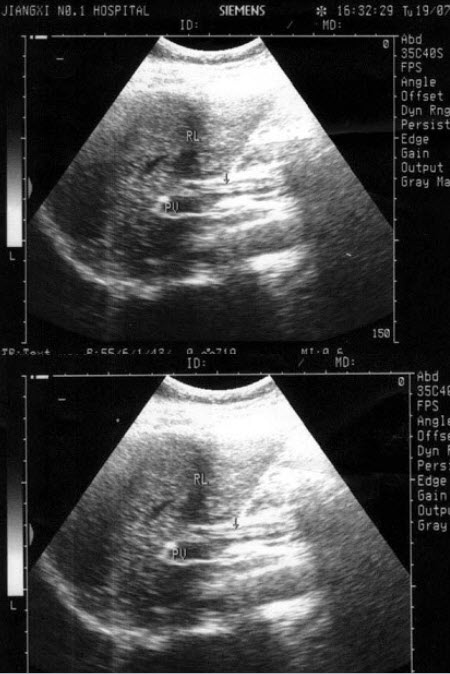

99、单项选择题

图示3所指部位()

A.脾静脉

B.腹主动脉

C.肠系膜上动脉

D.胰头

E.左肾静脉

100、单项选择题

105、单项选择题

图示4所指部位()

E.下腔静脉